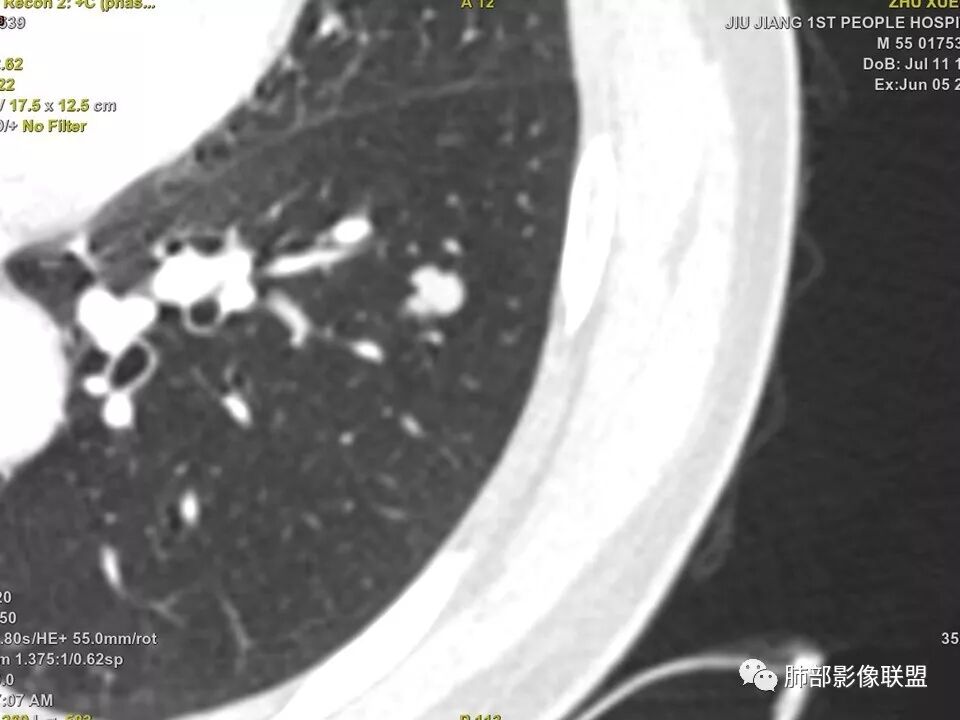

中年男性,左肺下叶不规则实性结节,有分叶及棘状凸起,支气管截断,轻度不均匀强化,考虑鳞癌,鉴别炎性肉芽肿。

左肺下叶前内基底段结节 深分叶和脐凹 表面部分膨隆 部分收缩 支气管截断 轻度强化 中央有坏死 考虑鳞癌 鉴别炎性结节

中年男性,支气管门口截断、邻近支气管未见管壁增厚,分叶明显,边缘彭隆,内见小坏死灶,周围未见GGO,考虑周围性鳞癌,鉴别炎性肉芽肿。

病灶多结节融合,有分叶,也支气管截断,有细小血管连接,考虑恶性结节,周围型肺癌。

左肺下叶前内基底段结节,轮廓凹凸不平,局部边缘平直,密度不均,近段支气管阻塞,增强前后CT值无明显变化,考虑肉芽肿,结核?腺癌代排

左肺下叶前基底段结节,病灶边缘分叶,边缘平直,u型征,可见气管截断,增强可见病灶边缘血管,平扫ct值低,轻度强化。考虑良性病变。

实性结节,以收缩为主,强化弱,支气管截断面呈凹面,浅分叶,肉芽肿性炎

支气管截断,结节轮廓凹凸不平,密度不均,无明显强化,部分边缘呈平直征,考虑结核性肉芽肿,腺癌代排